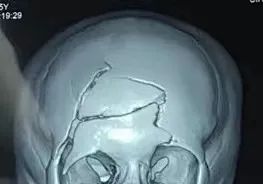

神经外科主任医师江辉接诊后发现患儿神志模糊,头部有一个长约3厘米的伤口,伤口内可以看到额骨粉碎性骨折,脑组织从骨折缝中流出。急诊头部CT显示其右额脑挫裂伤并血肿形成、额骨粉碎性骨折。

主任医师刘国平和江辉马上急诊为患儿行开颅术。术中,手术团队将患儿额骨的碎骨片取出,并在显微镜下彻底清除右额脑内血肿,止血后再行硬脑膜扩大修补,有效防止了术后脑组织外溢和脑脊液漏。术后,复查头部CT显示右额脑内血肿清除满意。术后三天,患儿神志转为清楚,四肢活动自如,并于三周后出院回家。

7月23日,由杨佳宁为患儿主刀的颅骨修补手术顺利完成。术后复查头部CT显示钛网固定牢靠,塑形满意。8月3日,患儿康复出院。